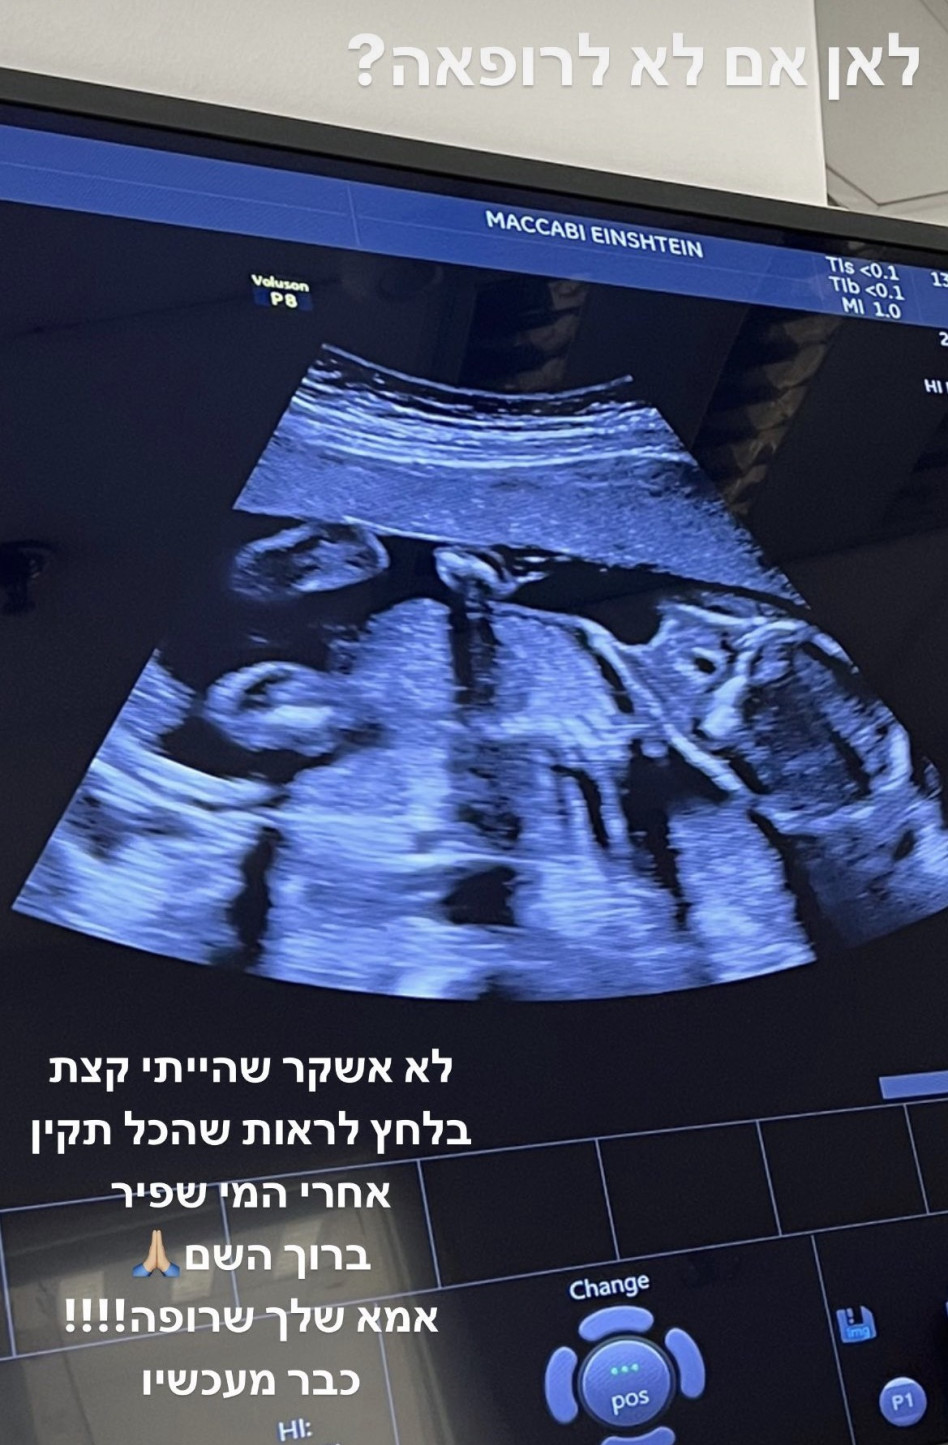

הביצה ממשיכה להתרחב וברשימת הכוכבות הנמצאות בהריון נמנית גם קורין גדעון, המטפחת בבטנה בייבי שני וצפויה בעוד מספר חודשים לבקר בפעם השנייה בחדר לידה ולהביא לעולם אח או אחות לבתה הבכורה אלונה. גדעון שאמנם רגילה לחשוף עם עוקביה רגעים רבים מחייה, עדיין לא חשפה את מין העובר המתפתח בבטנה, אך היא מתכוונת לעשות זאת בהקדם. אלא שאמש שיתפה תיעוד מבדיקת האולטרסאונד שעברה, רגע אחרי שעשתה בדיקת מי שפיר לעובר והעוקבות הנלהבות ניסו להתחכם דרך תצלום האולטרסאונד ולנחש מה מין העובר.

היו שראו איבר מין זכרי, והיו שטענו כי גדעון ובעלה חילי סורצקין מצפים לבת שנייה אחות לאלונה. האמא ההריונית מיהרה לעשות סדר בדברים וכתבה ״זה שכולכם נהייתם מומחי אולטרסאונד זה פיפי, אולי הייתי צריכה לאמץ את הטרנד החדש של טשטוש עוברים. קיצר לא רואים את המין בתמונה שהעלתי, אפשר לנשום עמוק ולהמתין בסבלנות״.

בן או בת? קורין גדעון (צילום: צילום מסך אינסטגרם)